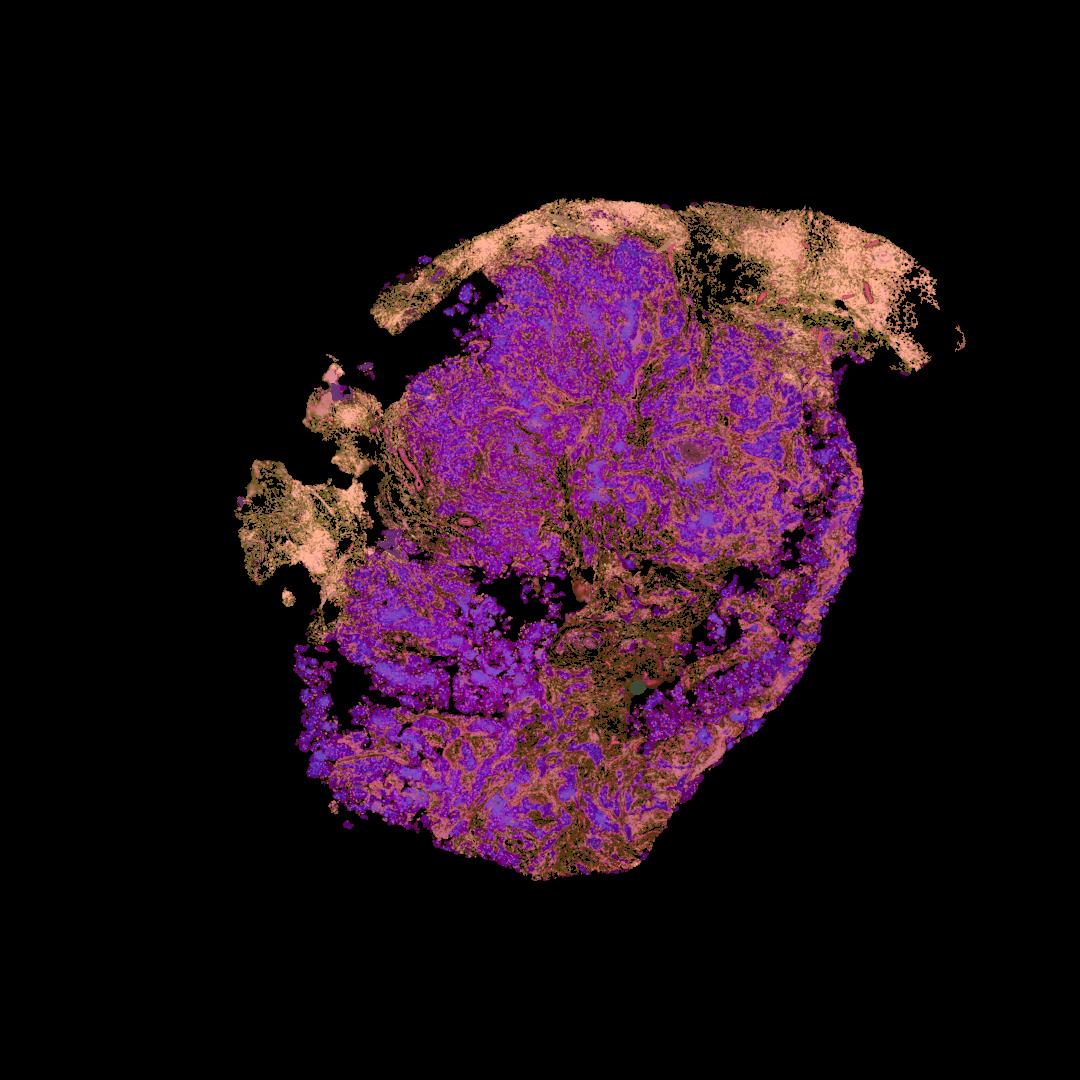

Atlas: Washington University

Breast cancer (BC) is defined by distinct molecular subtypes with different cells of origin. The transcriptional networks that characterize the subtype-specific tumor-normal lineages are not established. In this work, we applied bulk, single-cell and single-nucleus multi-omic techniques as well as spatial transcriptomics and multiplex imaging on 61 samples from 37 patients with BC to show characteristic links in gene expression and chromatin accessibility between BC subtypes and their putative cells of origin. Regulatory network analysis of transcription factors underscored the importance of BHLHE40 in luminal BC and luminal mature cells and KLF5 in basal-like tumors and luminal progenitor cells. Furthermore, we identify key genes defining the basal-like (SOX6 and KCNQ3) and luminal A/B (FAM155A and LRP1B) lineages. Exhausted CTLA4-expressing CD8+ T cells were enriched in basal-like BC, suggesting an altered means of immune dysfunction. These findings demonstrate analysis of paired transcription and chromatin accessibility at the single-cell level is a powerful tool for investigating cancer lineage and highlight transcriptional networks that define basal and luminal BC lineages.